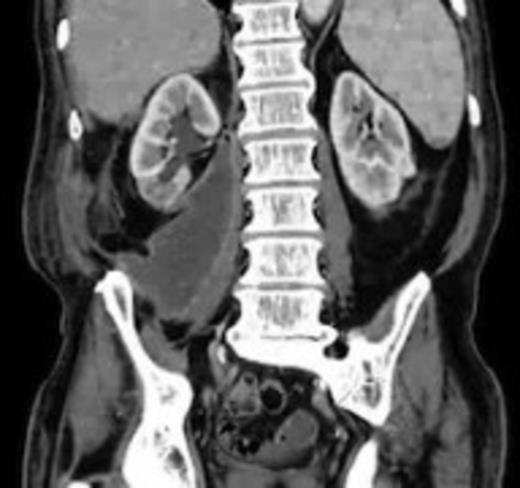

An 82 year old gentleman with known peripheral vascular disease and previous open popliteal aneurysm repair underwent endovascular repair of a 58mm infrarenal abdominal aortic aneurysm (Fig. 1) using a Cook Zenith bifurcated prosthesis The Zenith Flex® AAA Endovascular Graft (Cook Medical Inc., Bloomington, USA). The operation, which was performed under general anaesthetic and bilateral groin cut downs with intravenous prophylactic antibiotic cover on induction (Co-amoxiclav 1.2g) was uneventful. The main body was deployed via the right side. Completion angiograms showed satisfactory exclusion of the aneurysm sac with good graft position and no endoleaks. Post operatively the patient had a brief period of low grade pyrexia and lower abdominal pain that settled spontaneously. This was thought to be due to post implant graft reaction. Pre-discharge imaging with plain abdominal X-rays was deemed satisfactory.

A 50 mm maximum retroperitoneal collection situated between the right kidney and the right iliac vessels